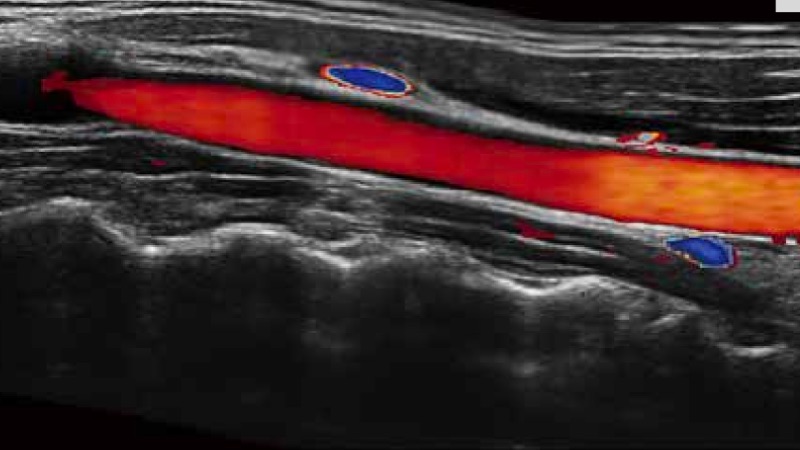

凭借开立医疗先进的成像技术和优异的探头技术提供的清晰的图像表现,您可以更自信地做出临床决策。